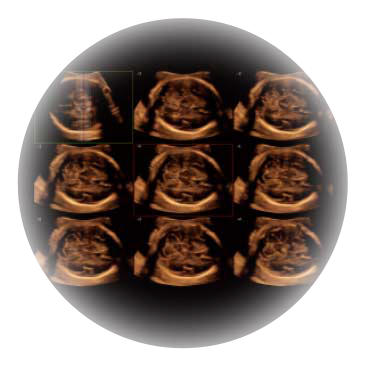

• M-Slice多切面成像

0.5mm厚度的薄层切片显像,可清晰显示微小病灶的连续断面。

• S-Live Silhouette光影成像

可同时显示组织结构表面和内部的轮廓信息,达到透视效果,为临床提供更丰富的诊断信息。

• 产科自动测量

自动获取标准切面,自动完成测量,帮助医生快速完成检查,同时提升测量准确性。